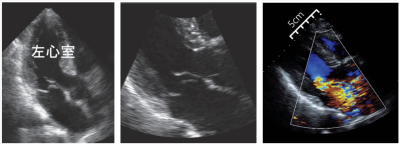

検査所見:血液所見:赤血球 442万、Hb 13.8 g/dL、Ht 42%、白血球 7,300、血小板 20万。血液生化学所見:LD 218 U/L(基準 120~245)、CK 70 U/L(基準 30~140)、尿素窒素 19 mg/dL、クレアチニン 0.8 mg/dL、血糖 158 mg/dL。心筋トロポニンT迅速検査陰性。胸部エックス線写真で肺うっ血を認めた。心電図と心エコー図とを別に示す。心エコー検査では左室駆出率は75%で、局所壁運動異常は認めず、僧帽弁後尖に線維状の構造物の付着を認めた。